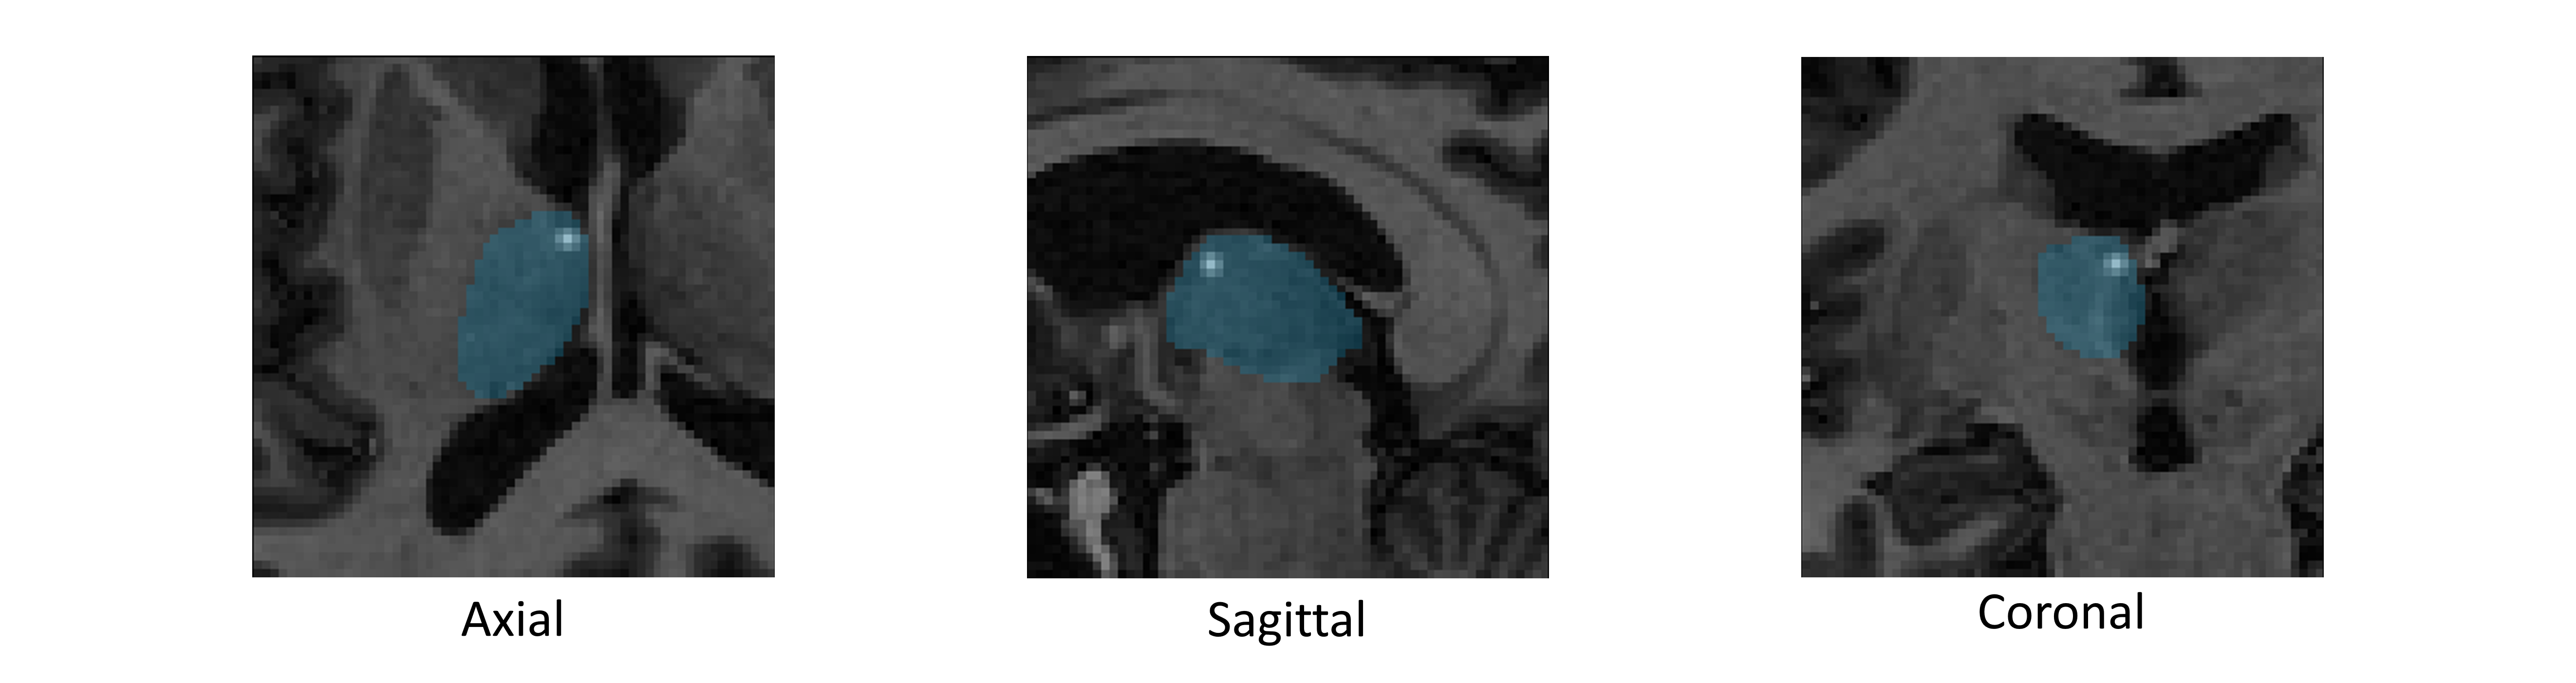

Epilepsy is the fourth most common neurological disorder and affects people of all ages worldwide. Deep Brain Stimulation (DBS) has emerged as an alternative treatment option when anti-epileptic drugs or resective surgery cannot lead to satisfactory outcomes. To facilitate the planning of the procedure and for its standardization, it is desirable to develop an algorithm to automatically localize the DBS stimulation target, i.e., Anterior Nucleus of Thalamus (ANT), which is a challenging target to plan. In this work, we perform an extensive comparative study by benchmarking various localization methods for ANT-DBS. Specifically, the methods involved in this study include traditional registration method and deep-learning-based methods including heatmap matching and differentiable spatial to numerical transform (DSNT). Our experimental results show that the deep-learning (DL)-based localization methods that are trained with pseudo labels can achieve a performance that is comparable to the inter-rater and intra-rater variability and that they are orders of magnitude faster than traditional methods.